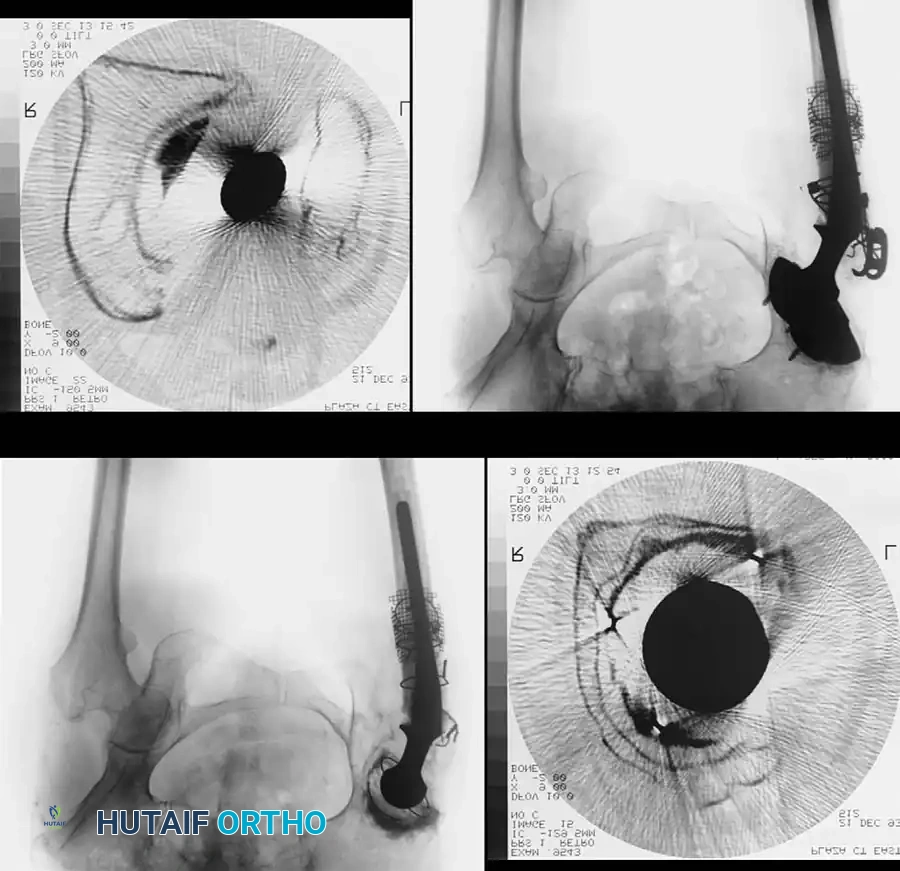

Radiographic Evaluation

High-quality, orthogonal radiographs of the pelvis and the entire femur are mandatory. Poor-quality imaging obscures the distinction between thinned cortical bone, osteolysis, and cement mantles.

* Magnification Markers: Essential for precise digital templating to anticipate the need for extra-small or jumbo components.

* Lateral Femoral Views: Must be assessed to evaluate the anterior bow of the femur. Mismatch between a long, straight revision stem and a bowed femur increases the risk of anterior cortical perforation.

* Advanced Imaging: Computed Tomography (CT) with metal artifact reduction sequences (MARS) is invaluable for assessing acetabular column integrity and pelvic discontinuity.

The Extended Trochanteric Osteotomy (ETO)

For complex femoral revisions, particularly those involving well-fixed cementless stems, varus remodeling, or extensive distal cement mantles, the Extended Trochanteric Osteotomy (ETO) is the gold standard.

ETO Technique:

1. Measure the required length of the osteotomy preoperatively (usually 12-15 cm, ensuring it bypasses the well-fixed portion of the stem).

2. Elevate the vastus lateralis anteriorly to expose the lateral femur.

3. Use an oscillating saw or high-speed burr to make the posterior and anterior longitudinal cuts.

4. Complete the distal transverse cut, ensuring rounded corners to prevent stress risers.

5. Lever the fragment open anteriorly, hinging on the intact anterior periosteum and vastus lateralis.